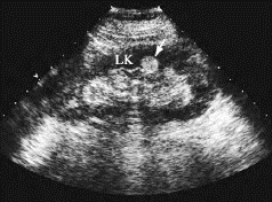

图29-9 肾细胞癌声像图

右肾中部包块(M),边界清楚,向外突出,内部为中等回声